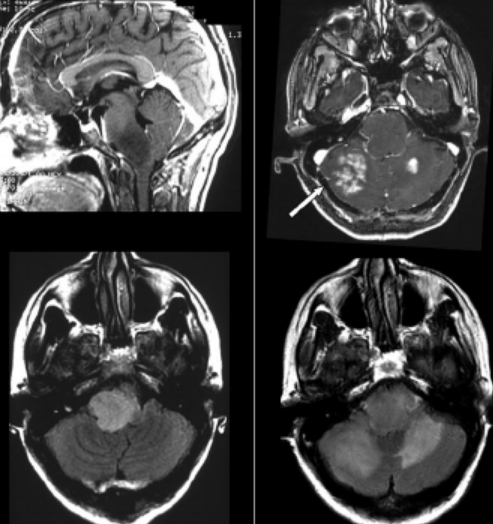

二級少突膠質(zhì)瘤能活30年嗎?一般來說,大部分二級少突膠質(zhì)瘤患者是難以活到30年的,只有少部分幸運的患者可能能活到三十年。少突膠質(zhì)細胞瘤是一種少見的腦內(nèi)腫瘤,它屬于一組叫做膠質(zhì)瘤的腦腫瘤。而膠質(zhì)瘤一共分為4級,級別越高惡性程度就越高,而2級膠質(zhì)瘤是偏良性的,不過2級膠質(zhì)瘤也很難治愈,所以存活30年的希望不大。1級膠質(zhì)瘤是完全良性的,如果能夠通過手術(shù)將腫瘤切除,有希望完全治愈,也就是有希望存活30年以上,甚至終生不再復發(fā),不影響到壽命,但對于二級少突膠質(zhì)瘤活到30年是比較難的。

在全部腦腫瘤中,大約3%的腦瘤是少突膠質(zhì)細胞瘤。腫瘤可以是快速生長,也可以是緩慢生長。

少突膠質(zhì)細胞瘤通常分為兩種類型:二級(生長緩慢)和間變性III級(快速生長和惡性)。

少突膠質(zhì)細胞瘤患者的預期壽命取決于腫瘤的分級和早期診斷。需要注意的是,每個人的情況是不同的,一般來說,II級少突膠質(zhì)細胞瘤患者在確診后可能存活12年左右。III級少突膠質(zhì)細胞瘤患者的平均預期壽命為3.5年。